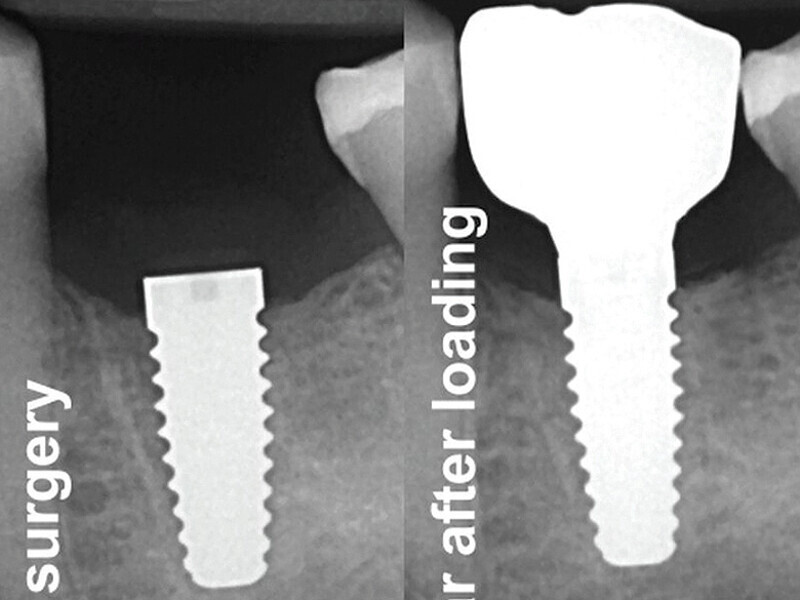

Fig. 13: X-ray control after surgery and one year post-loading. (Photo: Jens Tartsch, DMD)